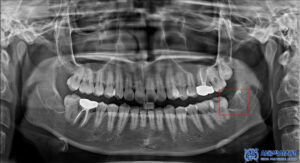

이렇게 전체적인 치료가 마무리되며

다수 충치 문제들이

모두 해결이 되었습니다.

치료 후 기능적·심미적인 부분을

함께 회복하여 일상적인

저작 활동에 불편함이 없도록 개선되었고

자연스러운 치아 형태와

색상도 되찾을 수 있었습니다.

마무리 후 사진입니다.

환자분께서는 충치 정도에 따라

정직하게 진단해주는 모습이 좋았고,

치료도 너무 잘 받아보셨다고 하셨습니다.

신경치료 진행하면서

많이 편해지셨다고 하셨고,

크라운 색상도 다른치아들과 자연스럽고

씌운것도 괜찮으시다고

만족해주셨습니다.